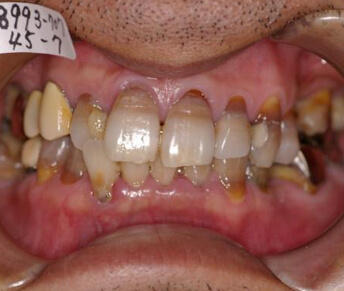

- マウスピース型矯正装置

メリット

- ・装置が目立たない。

デメリット

- ・日本矯正歯科学会の治療指針でも歯を抜いての矯正治療には推奨されていないように、治療効果に限界がある。

- ・歴史的に見ても同様な装置はいくつもありましたが、いずれも治療効果が低い為に時間の経過とともに使用されなくなっている。

- ・完成物薬機法対象外の矯正歯科装置であり、承認薬品を対象とする医薬品副作用被害救済制度の対象外となる場合がある。